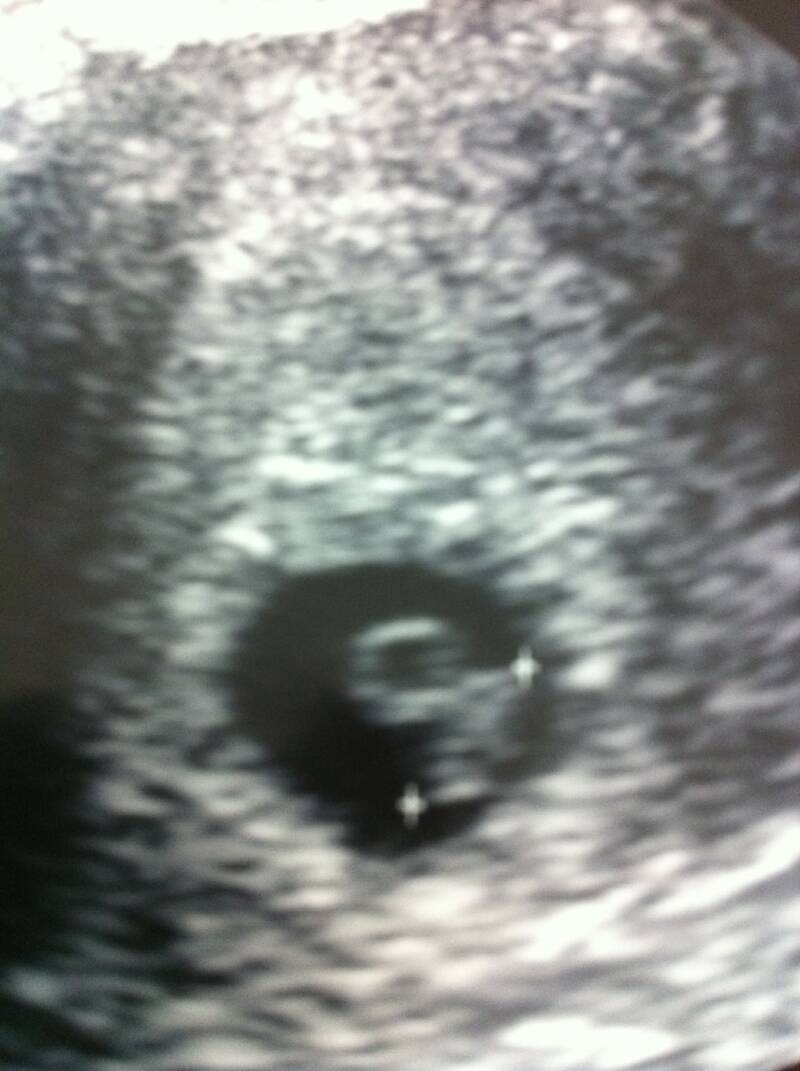

6 weeks, 4 days

Aubrey's thoughts: I think it looks like me already! :)9 weeks, 4 days

We got to see our little one's heartbeat that day!  This is all starting to feel so real....12 weeks, 2 days